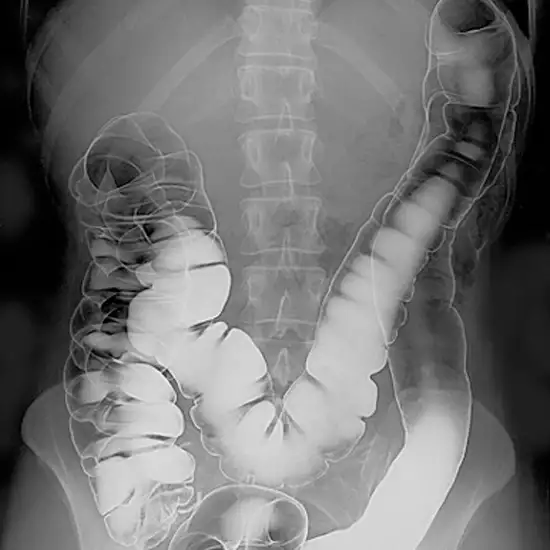

This imaging test takes X-rays of the colon and rectum while using two forms of contrast. The usage of two contrasting materials makes structures easily seen.

The radiologist will insert contrast material into your colon to drain out while only a thin layer will remain inside the colon wall. Then, air will be filled into the colon. The expanded colon provides detailed images of the inner colon.